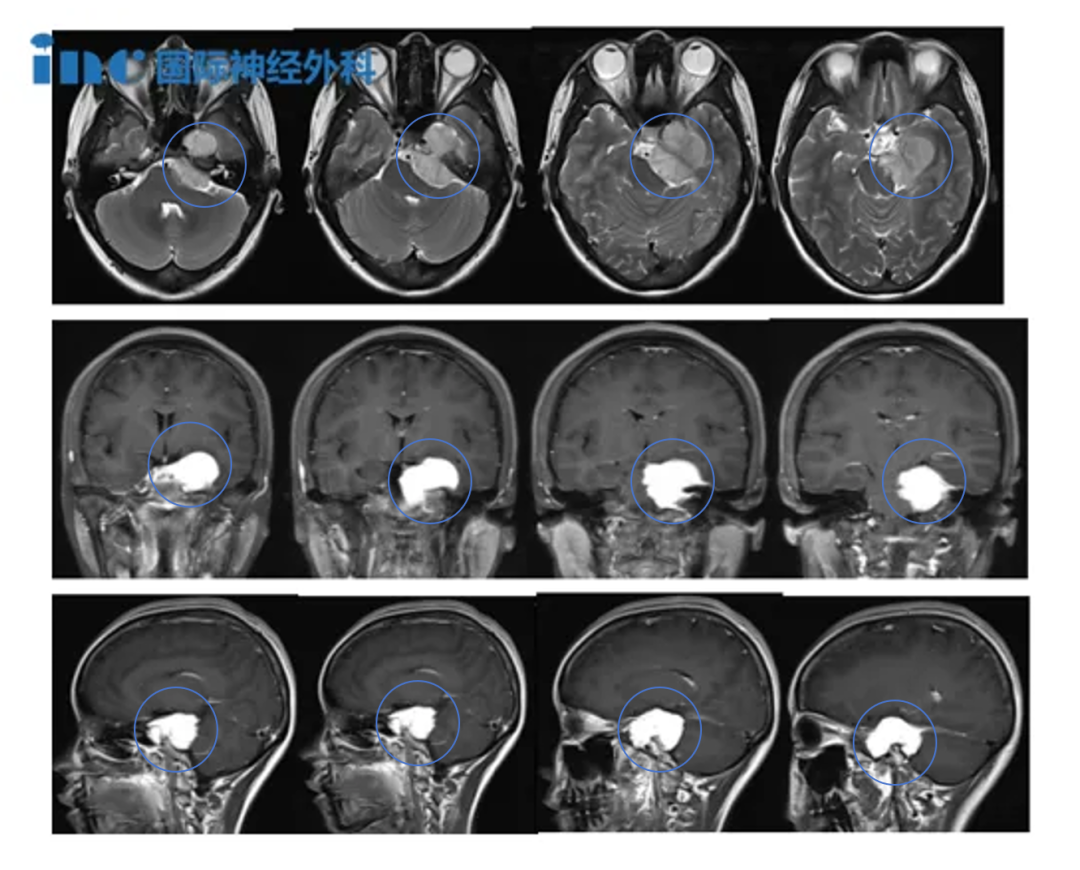

患者为75岁男性,因进行性头痛及共济失调数周在某一医院就诊,期间多次跌倒。症状评估期间头颅MRI显示起源于上斜坡的4.2×3.4厘米脑膜瘤。肿瘤占据桥前池大部,向上延伸至交叉池水平,向下达内听道,向外侧侵入右侧中颅窝。基底动脉被完全包裹,脑桥及脑干存在显着占位效应与水肿。

▼福洛里希教授岩斜区脑膜瘤患者术前术后手术症状改善